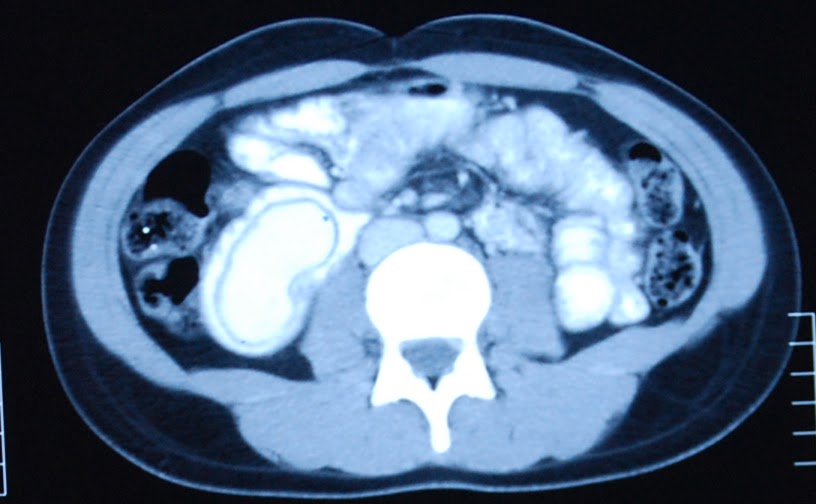

Windsock Deformity . Download original video (.6 mb) the “windsock sign” refers to the appearance of the intraluminal duodenal diverticulum on images from upper gastrointestinal barium series (1), but it is similar at abdominal ct and mri (2) when the diverticulum is distended. The “windsock” sign refers to the pathognomonic appearance of an intraluminal duodenal diverticulum, as seen on the upper. As in this case, a collapsed diverticulum can simulate an intraluminal mass at ct (3). The presence of a duodenal. The patient refused surgical excision of the diverticulum and elected for watchful waiting of his condition. The windsock sign is an important radiographic finding that can definitively diagnose the presence of an intraluminal duodenal web [2]. The “windsock sign” refers to the.

The windsock sign is an important radiographic finding that can definitively diagnose the presence of an intraluminal duodenal web [2]. The “windsock sign” refers to the. The patient refused surgical excision of the diverticulum and elected for watchful waiting of his condition. The “windsock” sign refers to the pathognomonic appearance of an intraluminal duodenal diverticulum, as seen on the upper. The presence of a duodenal. Download original video (.6 mb) the “windsock sign” refers to the appearance of the intraluminal duodenal diverticulum on images from upper gastrointestinal barium series (1), but it is similar at abdominal ct and mri (2) when the diverticulum is distended. As in this case, a collapsed diverticulum can simulate an intraluminal mass at ct (3).